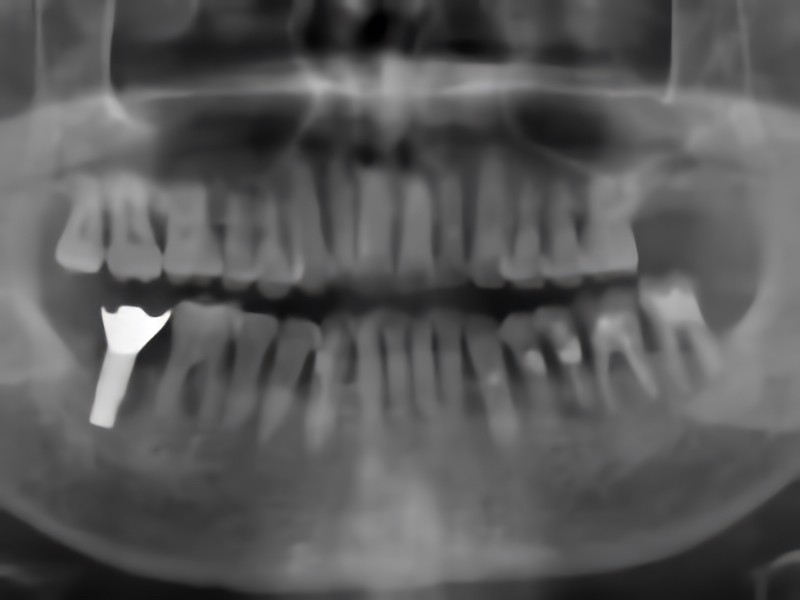

治療後のレントゲン写真

インプラントは、歯を失った部分の顎の骨に人工歯根を埋め込み、その上に人工歯を固定する治療方法です。ブリッジや入れ歯とは異なり、周囲の健康な歯を削る必要がないため、残っている歯への負担を抑えられる点が特長です。骨としっかり結合することで、自分の歯に近い噛み心地を目指せるため、食事や会話を自然に楽しみやすくなります。見た目の違和感が少ないことも選ばれる理由の一つです。

ただし、外科処置を伴うため、すべての患者様に適応できるわけではありません。糖尿病などの全身疾患がある場合や、顎の骨の量が不足している場合には、慎重な判断が必要です。そのため、治療前の十分な検査と説明が重要になります。

みさき歯科医院ではAQBインプラントシステムを採用し、お口の状態だけでなく全身の健康状態も確認したうえで治療計画を立てています。より高度な処置が必要と判断される場合には提携医療機関と連携し、安全性を最優先に対応しています。将来の生活まで見据えながら、患者様にとって無理のない選択肢を一緒に検討していきます。